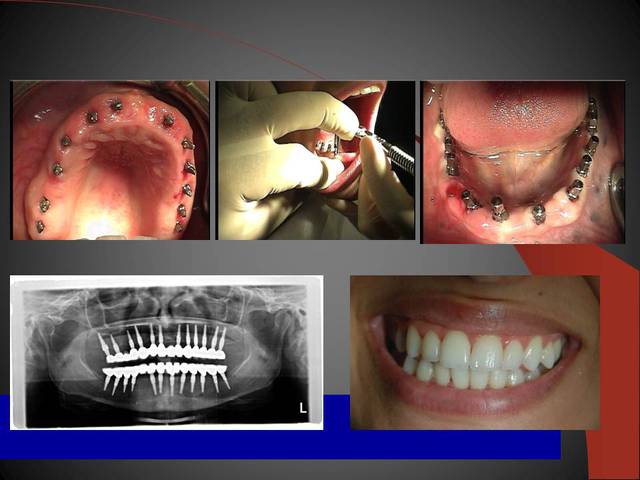

23 implants, rehabilitation totale

Un cas qui va sans doute prêter à discussions, juste pour montrer que la technique MIMI (non invasive) peut donner des résultats de qualité et esthétiques en moins de temps qu une chirurgie dite traditionnelle.

Les deux premières photos montrent le cas d´une jeune femme ( qui malheureusement s est fait retiré toutes les dents à l´étranger....).Ce cas a pu être terminé deux semaines après l´implantation.

3ème photo: radio d´un patient âgé de 73 ans qui souhaitait avoir des dents fixées.Comme on l´observe il n a plus de place après les foramines mentales.Nous avons donc utilisé juste l´os interforaminal. Nous avons suivi le concept du prof. Nentwig qui consiste à pouvoir ajouter 2 dents dans chaque quadrant dans la mandibule.

Je sais bien que 8 implants auraient suffit cependant 10 ont été posés.Nous voulions remplacer chaque racine avec un implant.

Les deux dernières photos montrent le même cas deux ans plus tard.